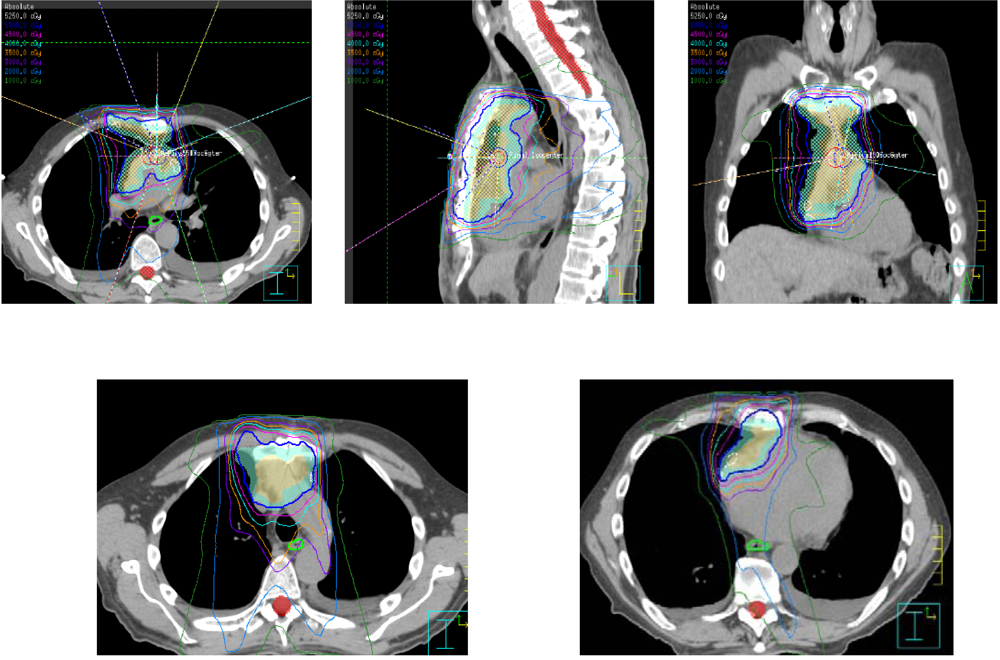

From pubs.rsna.org

Role of Imaging in the Diagnosis, Staging, and Treatment of Thymoma Is Thymoma Cancer Curable There’s also a much rarer form of thymus gland cancer called thymic carcinoma. An advanced thymoma may be categorized as thymic cancer, which tends to be more aggressive—and more likely to recur—than thymoma. Cancer of the thymus gland is rare. Thymomas are cancerous tumors that grow in. Thymoma staging can help doctors determine your best treatment options. Most cancers that. Is Thymoma Cancer Curable.

Role of Imaging in the Diagnosis, Staging, and Treatment of Thymoma Is Thymoma Cancer Curable Surgery is the primary treatment for thymoma. Thymoma is a rare cancer and like all cancers, it can be serious. Cancer of the thymus gland is rare. There’s also a much rarer form of thymus gland cancer called thymic carcinoma. Thymoma and thymic carcinoma treatment options include surgery, radiation therapy, chemotherapy, chemoradiation, and. Thymoma staging can help doctors determine your. Is Thymoma Cancer Curable.